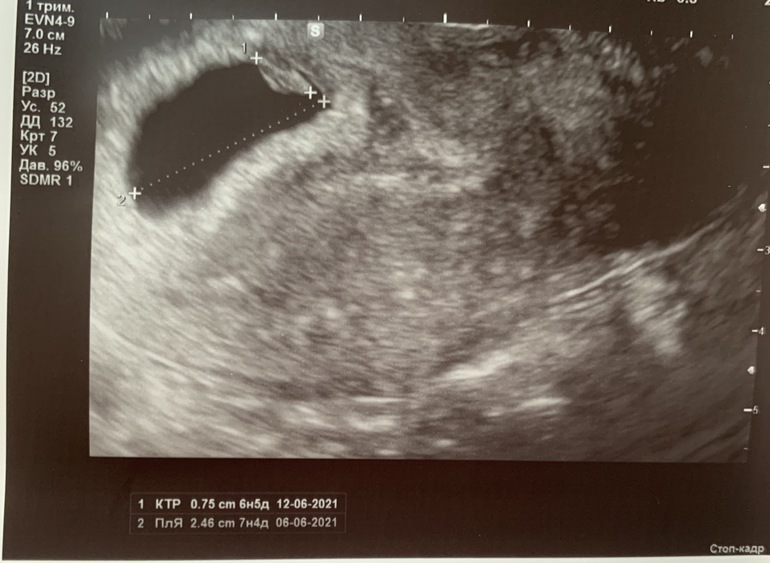

Ну что, кто спец по методу рамзи 😀

Счас дам 3 фото, узи во всех случаях вагинальное, срок по М 7-8 недель :)

Кто сейчас?

Смотрят место прикрепления - если по правой стороне, то девочка, если по левой, то мальчик.

Вообщем типа от места прекрерления ребёнка, можно с большей вероятностью угадать пол ребёнка :) но я не понимаю как смотреть, от чего зависит и тд 😂 там вроде если узи вагинальное, то надо как то зеркально смотреть, вообщем мне не понять :)